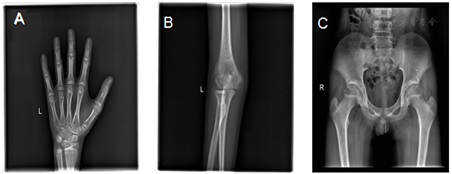

心电图提示窦性心律不齐。胸片提示心肺未见明显异常。骨龄片提示相当于16~17岁左右(图1)。第2~4腰椎椎体骨密度值减低(全部Z值-4.5,最低-5.3),提示骨质疏松;左髋关节、大转子密度值在正常范围(全部Z值-0.5,最低-1.5)。心脏彩超:心脏结构及功能未见明显异常。乳腺彩超提示男性乳腺未见明显占位性病变。阴囊彩超提示双侧睾丸体积偏小(切面内径左侧约14.2 mm×6 mm×9.9 mm,右侧约15 mm×5.9 mm×10.9 mm)。全腹彩超:前列腺体积稍小(大小约14 mm×10 mm×13 mm)。肝、胆、胰腺及腹膜后所见部位、脾、双肾、双输尿管、膀胱未见明显占位性病变。腹主动脉所见部位未见明显异常。垂体+嗅球、嗅束磁共振:垂体MRI平扫及增强未见明显异常;双侧嗅沟存在、显示稍小,双侧嗅球、嗅束未见显示(图2)。

注:A:左腕关节;B:左肘关节;C:髋关节;骨龄片提示相当于16~17岁左右,与年龄相当